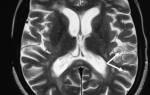

Методы и способы диагностики

Поскольку основные признаки заболевания проявляются в совокупности, диагностика не представляет особой сложности. Эффективность лечения во многом зависит от своевременного определения клинической картины и различения симптомов болезни от психосоматических проявлений.

Комплекс диагностических мероприятий для оценки сосудистого тонуса включает следующие процедуры:

- анализ состояния сосудов головного мозга с помощью реоэнцефалографии;

- ультразвуковое исследование периферических и артериальных сосудов;

- проведение электрокардиограммы для отслеживания динамики состояния;

- электроэнцефалография.